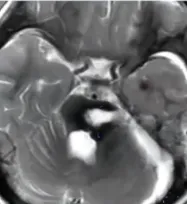

3岁半的患儿,因脑干海绵状血管瘤破裂出血而产生一个巨大血肿,紧紧包裹住脑干,导致小女孩已经出现严重的右侧偏瘫,她无法独自站立行走,小小年纪便要面临严重的生命威胁。

转诊至巴教授所在的医院,女孩家人守在手术室外焦急等待。巴教授谨慎地通过颞下入路进入桥脑的侧面,血肿最终成功清除,而桥脑后方的结构也完全保留,这对于小女孩将来的生活质量非常重要,意味着术后的她不会产生任何额外的功能损伤。